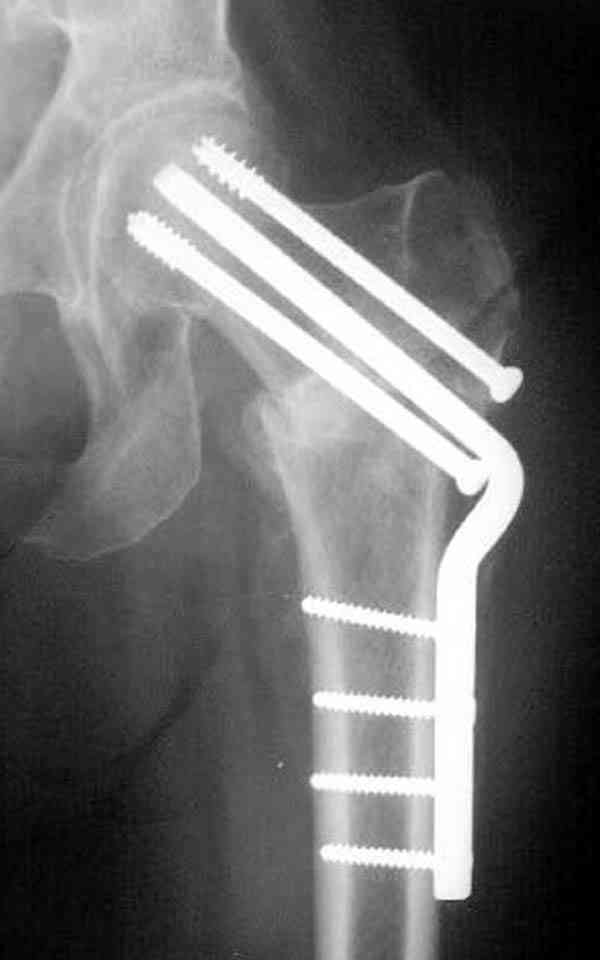

В идеале для профилактики рефрактуры шурупы надо вводить не больше, чем под 130 градусным углом и не ниже уровня малого вертела.

Насчет биомеханических преимуществ одного шурупа тоже возникает вопрос. Если придерживаться канонов механики, для перелома шейки необходимо 3 паралельных шурупа, расположенных ближе к кортикальному слою шейки.

Здесь случай перелома из-за ослабления латерального кортекса через 3 недели после операции на шейке. Шурупы были установлены под большим углом, слабый латеральный кортекс не выдержал нагрузку.